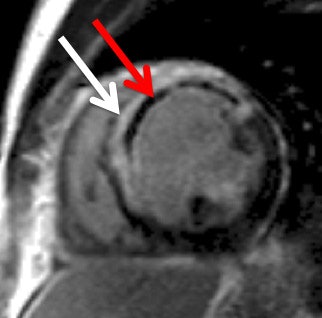

Late gadolinium enhancement image shows a large anteroseptal myocardial infarction (white arrow) with a central core of microvascular obstruction (red arrow). Images courtesy of Dr. Mark Westwood.

Late gadolinium enhancement image shows a large anteroseptal myocardial infarction (white arrow) with a central core of microvascular obstruction (red arrow). Images courtesy of Dr. Mark Westwood."Cardiac MRI provides reliable anatomical and functional assessment of the heart and evaluation of myocardial viability and coronary artery disease," he explained. "It is especially useful for diagnosing myocardial infarction. Cardiac MR late gadolinium enhancement can quantify the size, location, and transmural extent of the infarct."